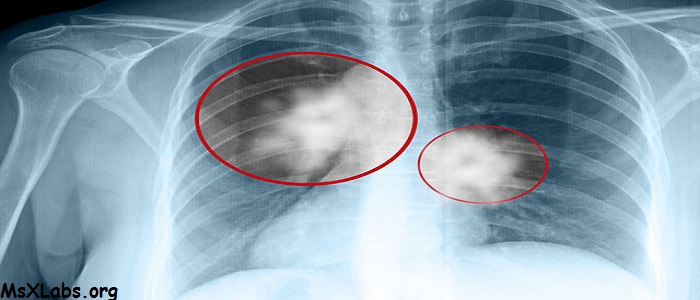

Akciğer Kanseri nedir?

Akciğer vücudumuzun oksijen gereksinimini sağlayan organımızdır. Her organ gibi akciğerimiz de birçok hücreden oluşur. Bu hücreler akciğerin normal olarak görevini yapabilmesi için ihtiyaç doğrultusunda bölünerek çoğalırlar. Akciğer kanseri, yapısal olarak normal akciğer dokusundan olan hücrelerin ihtiyaç ve kontrol dışı çoğalarak akciğer içinde bir kitle (tümör) oluşturmasıdır. Burada oluşan kitle öncelikle bulunduğu ortamda büyür, daha ileriki aşamalarda ise çevre dokulara veya dolaşım yoluyla uzak oranlara yayılarak (karaciğer, kemik,beyin vb. gibi) hasara yol açarlar. Bu yayılmaya metastaz adı verilir. Akciğer kanserleri mikroskop altında izlenen hücrelerin görüntüsüne göre iki ana guruba ayrılır. 1. Küçük hücreli (yulaf hücreli) akciğer kanseri 2. Küçük hücreli-dışı akciğer kanseri. Bunlar mikroskop altında izlenen kanserli hücrenin görüntüsüne göre ayrılıır.